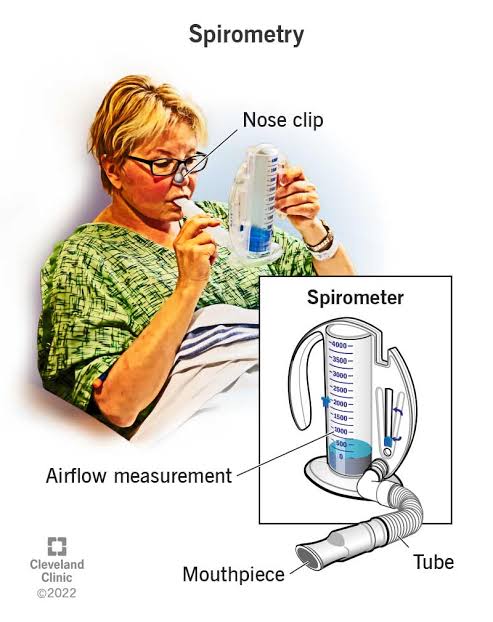

Spirometry (સ્પાઈરોમેટ્રી):

- સ્પાઈરોમેટ્રી એ એક પ્રકારનું લંગ ફંક્શન ટેસ્ટ છે જે આપણે કેટલી અમાઉન્ટમાં એર ઇન્હેલ અને એક્સેલ કરીએ છીએ તે મેઝર કરે છે આ ઉપરાંત કેટલા રેટથી (ફ્લો થી) ઇન્હેલ અને એક્સેલ કરીએ છીએ તે મેઝર કરે છે.

- સ્પાઈરોમેટ્રી ટેસ્ટમાં સ્પાઈરોમીટર ઇન્સ્ટ્રુમેન્ટનો ઉપયોગ કરવામાં આવે છે જેમાં ટ્યુબ દ્વારા માઉથ પીસ કનેક્ટેડ હોય છે અને આ માઉથ પીસ દ્વારા પેશન્ટની એર ઇન્હેલ અને એક્સેલ કરવાનું કહેવામાં આવે છે અને સ્પાઇરોમીટરમાં થતા ચેન્જીસને ઓબ્ઝર્વ કરવામાં આવે છે.

- આ ટેસ્ટ કરતી વખતે નોઝને ક્લિપ કરી દેવામાં આવે છે.

- સ્પાઈરોમેટ્રીની મદદથી રેસ્પાયરેટરી કંડીશન જેમ કે અસ્થમા અને COPD ને અસેસ કરી શકાય છે.